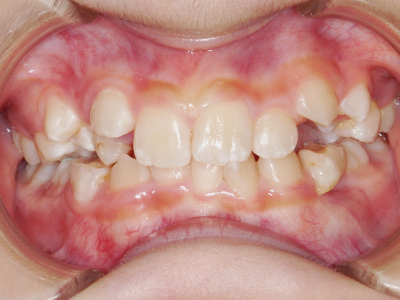

歯並びの相談に来られるお子様は、口呼吸をしているケースが多く、これが歯並びに大きな影響を与えています。

- 口呼吸をしている

↓ - 舌の位置が悪くなる

↓ - 頬の圧力が上の歯列にかかりやすくなる

↓ - 上あごが狭くなる

↓ - 下あごが狭くなる・下あごの位置が悪くなる

↓ - さまざまな不正咬合が生じる

ないき歯科クリニックでは、上あごの成長不足を補い、鼻呼吸を獲得しつつ歯列を整え、将来のお口をより健康な状態にすることをゴールに定める矯正治療をおこなっています。